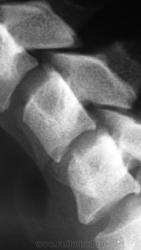

Дело в том, что именнов этом ПДС, определяется фиксация и ограничение объёма движений. Как видите - ни при згибании, ни при разгибании ширина и форма межпозвонкового диска не изменяется. Да и форма тела С5 мне кажется весьма отличной от других тел... Такое впечвтление, что сформирован неоартроз.

Там действительно есть неоартроз с деф артрозом, но  это точно не сами позвонки, а части избыточно развитых отростков...

Спасибо Анатолий Иванович, понял что это гиперплазированные поперечные отростки тел С5 и С6, с сформированым между ними неартрозом и деф. артрозом. Вообще эта пациентка какаято странная - жалуется на похудение одной (правой) половины тела. Напрвляли её на ПКОП - ничего кроме сколиоза, с небольшим торсионным компонентом нет. Тут вот шейный отдел, надо бы грудной снять, а тут опять кто то из врачей сказал, что много уже рентгена и на грудной не направили...